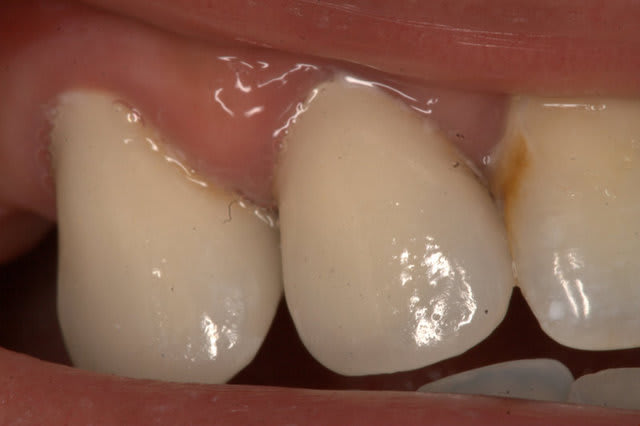

Le mien me sort ça en CCM pour 80 € (12 13). L'autre photo c'est un onlay composite transitoire Adoro sur la 11, 45 €. (Mon capteur photo est sale, je sais)

Il bosse à 5 km du cabinet, petite structure, excellents rapports.

J'en suis satisfait, avec l'expérience je lui trouverai peut être des limites. Franchement, en début de carrière je ne me vois pas bosser avec des labos qui exportent. Pour moi on ne peut pas raler contre le tourisme médical et faire faire sa prothèse à l'étranger. Mais bon quand on est jeune on a des principes...